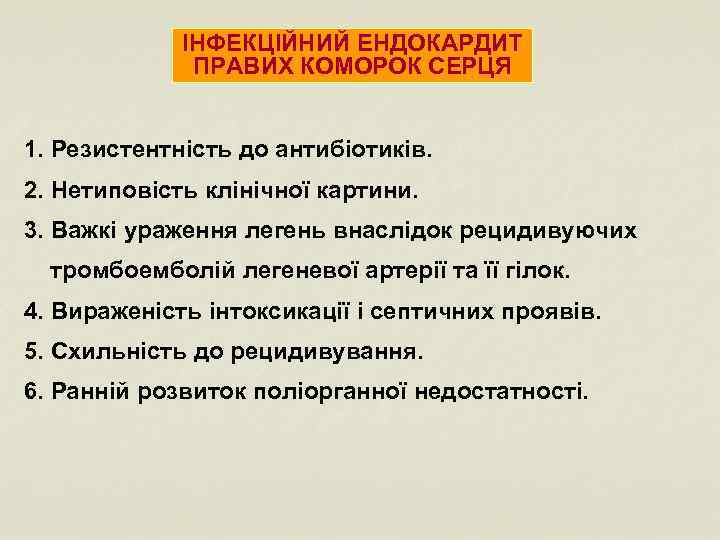

ІНФЕКЦІЙНИЙ ЕНДОКАРДИТ ПРАВИХ КОМОРОК СЕРЦЯ 1. Резистентність до антибіотиків. 2. Нетиповість клінічної картини. 3. Важкі ураження легень внаслідок рецидивуючих тромбоемболій легеневої артерії та її гілок. 4. Вираженість інтоксикації і септичних проявів. 5. Схильність до рецидивування. 6. Ранній розвиток поліорганної недостатності.